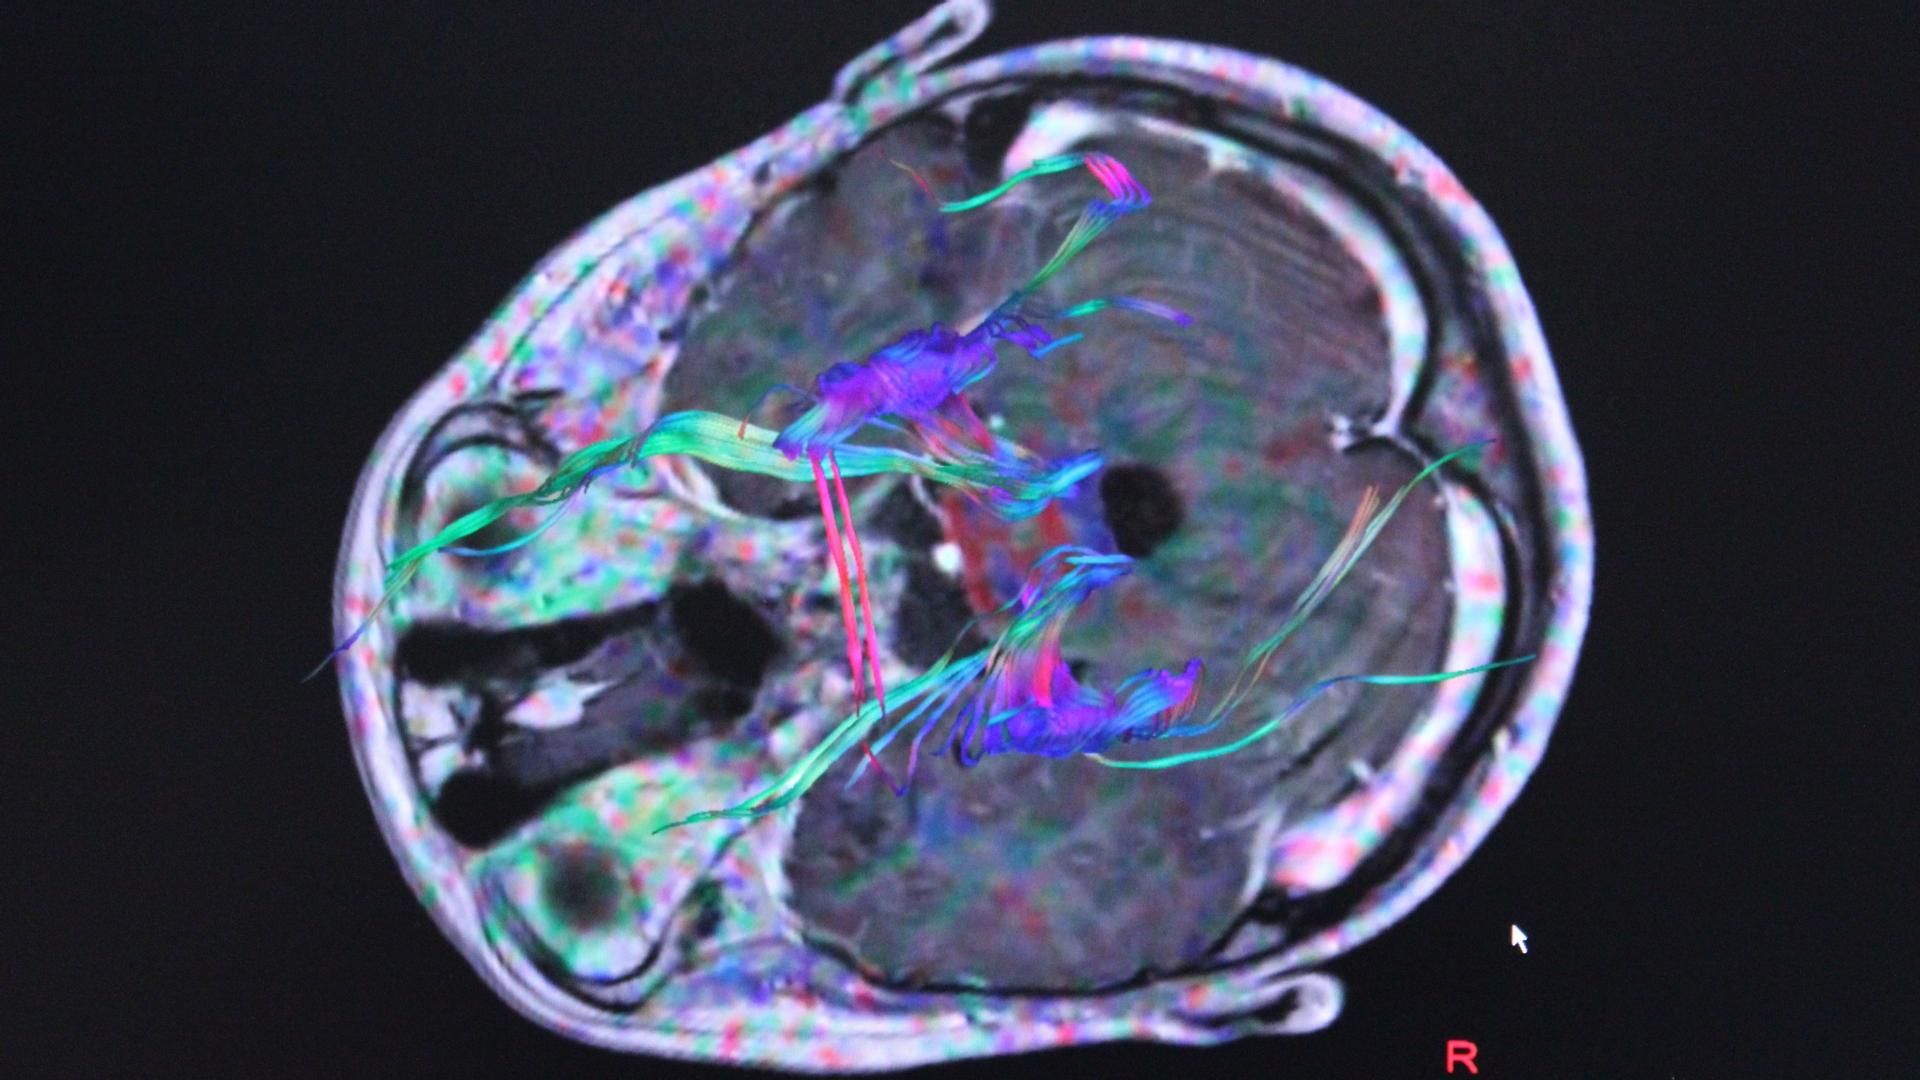

El estudio, publicado en la revista 'Nature Medicine', ha demostrado que la mencionada prueba permite detectar pequeñas cantidades de la proteína tau propensa a aglutinarse, así como sus formas patológicas mal plegadas que pueblan el cerebro, el líquido cefalorraquídeo y "posiblemente" la sangre.

A través de herramientas de Bioquímica y Biología Molecular, los científicos han identificado una región central de la proteína tau que es necesaria para la formación de ovillos neurofibrilares, ayudando a reconocer las proteínas tau propensas a la agregación y así ayudar a realizar un diagnóstico y tratamiento temprano.

Concretamente, los sitios de fosforilación, 'p-tau-262' y 'p-tau-356', pueden informar con precisión el estado de la agregación de tau en etapa temprana que, con una intervención adecuada, podría revertirse.

Como la patología de beta amiloide a menudo precede a las anomalías de tau en la enfermedad de Alzheimer, la mayoría de los esfuerzos de biomarcadores se han centrado en la detección temprana de cambios de beta amiloide; sin embargo, es la aglutinación de la proteína tau en estructuras, conocidas ovillos neurofibrilares, la que funciona como un "evento mas definitorio" del alzhéimer, ya que está más fuertemente asociado con los cambios cognitivos observados en las personas afectadas.